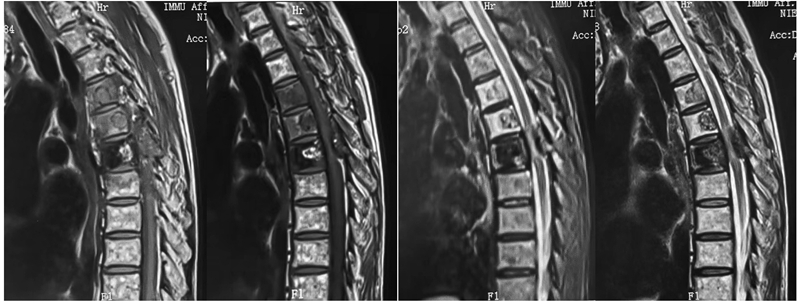

图1b MR显示T4-6椎体、T6左侧椎弓及L3椎体溶骨破坏,T1WI上为不均匀低信号,T2WI压脂上显示等低信号,周围骨髓水肿,其中T6椎体见斑片状双低信号,后方肿瘤压迫脊髓